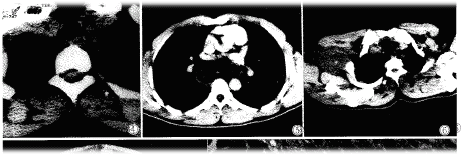

纵隔内神经鞘瘤,除1例位于椎体前方外,其余均位于脊柱两旁,边缘光滑,宽基底与脊柱相连,密度一般均匀(图4),2例呈低密度(类似水样密度)CT值13-19Hu,其余8例密度均匀低于或等于肌肉密度,增强扫描1例无强化(图5),4例不均匀强化。胸椎及肋骨骨质未见明确破坏和吸收,肿瘤未侵入椎管内。

臂丛神经鞘瘤呈圆形,类圆形软组织块影,位于臂丛神经走行区或与之关系密切的部位,CT平扫肿块低于或略低于肌肉密度(图6),边缘光滑。增强扫描高于肌肉低于血管。

腹部神经鞘瘤来源较复杂,11例中肝1例,胰腺1例,胃2例,其余7例位于腹壁及腹膜后椎旁。腹部神经鞘瘤因发生的组织器官不同,CT表现差异较大。本组腹部恶性神经鞘瘤,CT征象为肿瘤体积大,大部分边缘光滑,但不规则,有的与周围组织分界不清,粘连,密度不均,中心见更低密度灶(出血、液化、坏死),增强扫描均呈不均匀强化(图7)。

图1腰5椎管内神经鞘瘤椎间盘突出术后二年,腰5右侧神经根增粗,呈圆形软组织密度影。图2颈7椎管内神经鞘瘤,脊髓向前受压变扁,蛛网膜腔增宽扩大。图3颈动脉鞘区偏后神经鞘瘤,增强扫描强化不均匀,血管受压向前移位。图4纵隔神经鞘瘤宽基底与脊柱相连,边缘光滑,密度均匀。图5纵隔神经鞘瘤增强扫描,边缘轻度强化,中心不强化。图6臂丛神经鞘瘤,边缘光滑,密度均匀。图7腹腔恶性神经鞘瘤,肿瘤不规则,密度不均,见大片液化坏死区。图8神经鞘瘤病理见瘤细胞呈栅栏状改变(×40)